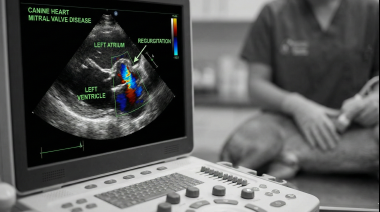

Entre los temas que se clasificaron como de mayor prioridad, se identificaron ocho categorías de investigación, muchas de las cuales demuestran la complejidad de los factores interrelacionados que afectan tanto a las personas como al bienestar de los perros. Entre ellos se incluyen cuestiones relacionadas con el comportamiento canino, la propiedad, los factores sociales, la crianza y el suministro, las enfermedades relacionadas con la raza, la importación, la práctica clínica y el bienestar en los refugios. Al identificar estos temas, los participantes también priorizaron las áreas de investigación diseñadas para tener el mayor impacto, con un fuerte enfoque en los asuntos que investigan los factores humanos en el bienestar canino.